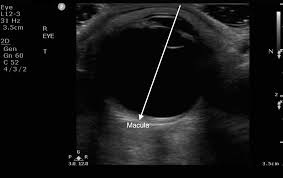

Ocular Ultrasound

Ocular ultrasound (echography) is a safe, non-invasive, bedside diagnostic tool used to image the eye's structures, particularly when the retina is obscured by blood or cataracts.